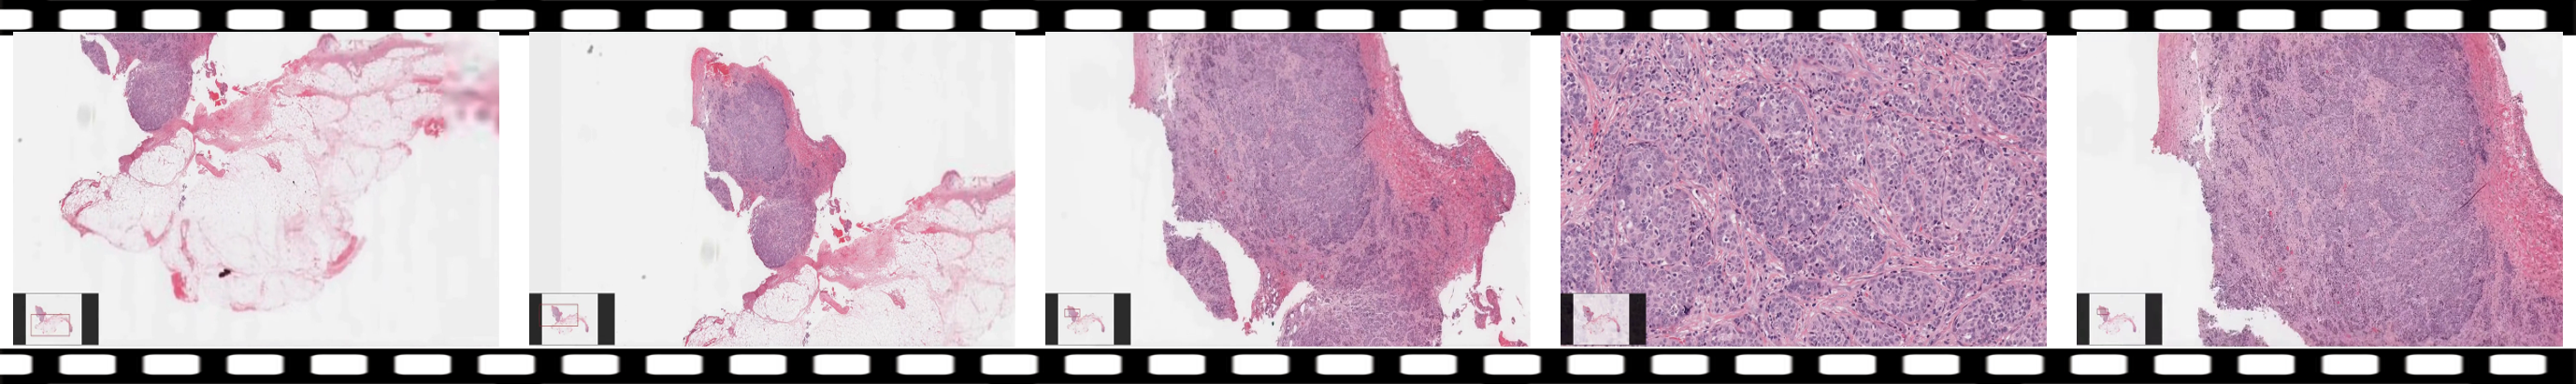

| Visual input example: Visual description and diagnosis | |

![]() |

|

| User | Q: What is the best diagnosis for the ovary/fallopian tube tissue? First, describe the image’s information relevant to the question. Then, provide your answer. |

| A: The image displays histological sections predominantly composed of malignant epithelial cells, characterized by marked cellular pleomorphism and high mitotic activity. The nuclei exhibit irregular contours, with prominent macronucleoli. There is evidence of atypical mitotic figures and a nested architectural pattern within the tissue. The background may contain desmoplastic stroma, which is indicative of invasive behavior. The proliferation of atypical cells alongside the high mitotic count supports the diagnosis of a high-grade neoplasm, likely of ovarian origin. | |

| Diagnosis: High-grade serous carcinoma | |

| GPT-4o | The images show a histological section of tissue with a dense cellular area. The cells appear to be arranged in nests and sheets, with a high nucleus-to-cytoplasm ratio, and there is evidence of mitotic activity. The stroma is fibrous and there is a clear demarcation between the tumor and surrounding tissue. |

| Based on these features, the best diagnosis for this ovary/fallopian tube tissue is a "serous carcinoma," which is a type of epithelial ovarian cancer characterized by these histological patterns. | |

| Score: (Context/correctness/detail): 4 5 4 (GPT-3.5-turbo-0613) | |

| VideoPath-LLaVA (Ours) | The image shows a histological section of the fallopian tube exhibiting features consistent with serous carcinoma. The epithelium is characterized by a papillary architecture, which is typical for this type of tumor. The cells are arranged in a complex pattern, forming multiple layers and displaying significant nuclear atypia. The nuclei are enlarged and irregularly shaped, indicating high-grade malignancy. There is also evidence of increased mitotic activity, further supporting the diagnosis of a malignant process. The stroma appears desmoplastic, which is often associated with invasive tumors. Overall, the histopathological features observed are indicative of a high-grade serous carcinoma. |

| Diagnosis: High-grade serous carcinoma of the fallopian tube. | |

| Score: (Context/correctness/detail): 5 5 4 (GPT-3.5-turbo-0613) | |

Qualitative Results. To further illustrate our findings, we present a qualitative comparison of VideoPath-LLaVA and GPT-4o on a representative example from the test set. This example reflects the general trends observed in our quantitative evaluation (Table 3), where VideoPath-LLaVA outperforms GPT-4o in identifying key histopathological features and diagnostic accuracy.